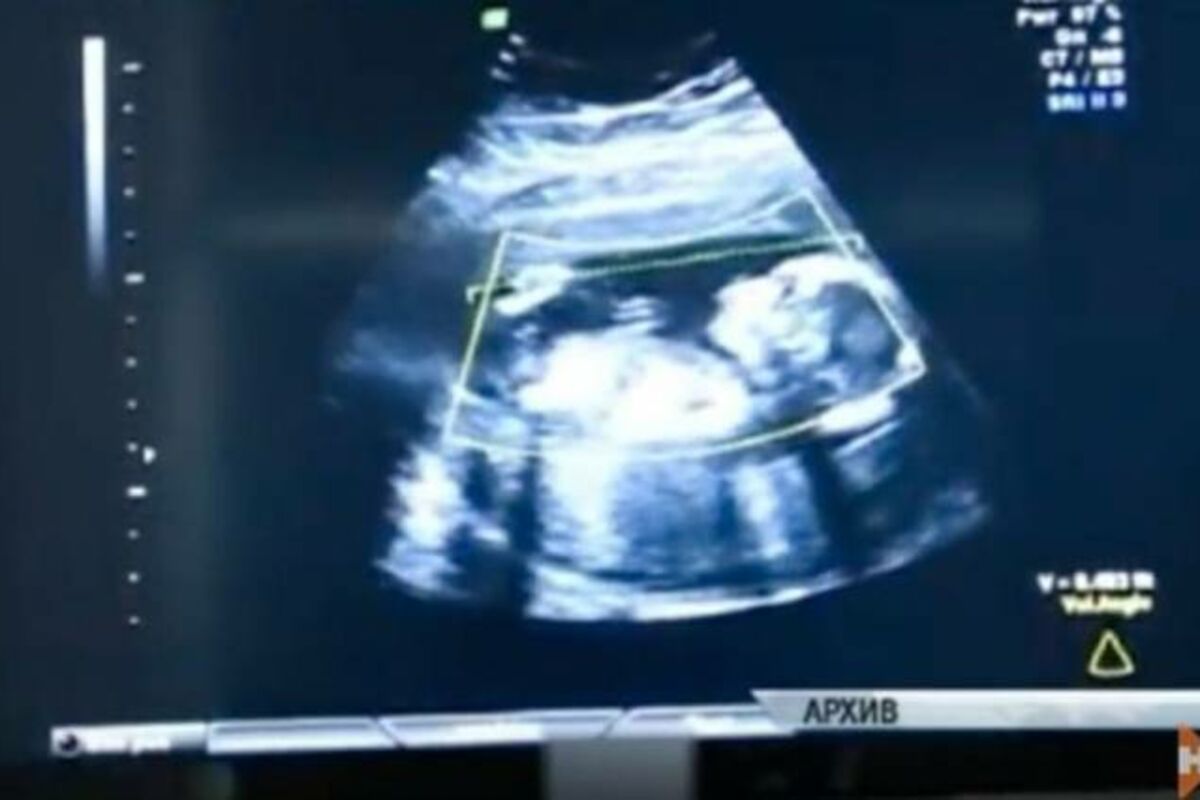

Dete se nije usadilo u matericu, već u trbušnu duplju majke. Ovakav slučaj spada u venmateričnu trudnoću, pri kojoj se oplođena jajna ćelija, umesto u matericu, usadi na drugom mestu. Međutim, trbušna duplja je gotovo nemoguće mesto za usađivanje.

Dete su hitno izvadili, a operacija je bila jako rizična za majku i za dete. Zapravo, u ovakvim slučajevima su prognoze vezane za preživljavanje veoma loše. Operacija je traja 2 sata, mnogo duže nego regularan carski rez.

Kada su lekari uspeli da izvuku dete, desilo se pravo čudo! Devojčica je disala, bila je odličnog zdravlja, a bila je teška čitava 4 kg! Ponosna majka je rešila da devojčicu nazove Veronika, što znači pobednica.